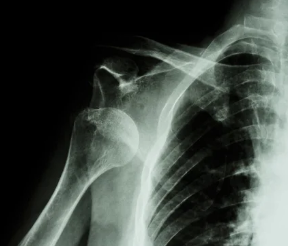

Instabilité d'épaule

La luxation d'épaule est une pathologie fréquente. En général secondaire à un traumatisme à haute intensité chez un patient jeune et sur chute simple chez le sujet agé.

La luxation est la perte de contact entre les surface articulaire